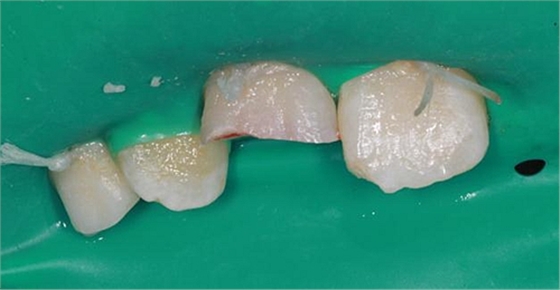

未行麻醉,上橡皮障,給予無(wú)菌鹽水沖洗露髓點(diǎn),可見(jiàn)露髓點(diǎn)滲血,于是給予充分止血,光固化氫氧化鈣蓋髓(voco)(首選MTA蓋髓,但是單位沒(méi)有該材料,只能退而求其次),酸蝕牙釉質(zhì),涂布自酸蝕粘結(jié)劑,斷端碎片給予牙釉質(zhì)全酸蝕,涂布自酸蝕粘結(jié)劑,雙固化樹(shù)脂粘結(jié)固定斷端。最后給予初步拋光。患兒家長(zhǎng)表示滿意。

術(shù)后A1粘結(jié)斷端處可見(jiàn)接縫,建議患兒擇日進(jìn)行樹(shù)脂修復(fù),同時(shí)恢復(fù)B1切角。因此患兒情況特殊,根尖未閉合,無(wú)法進(jìn)行去髓,故牙髓存在壞死感染可能,醫(yī)囑定期復(fù)查,如有情況及時(shí)處理。